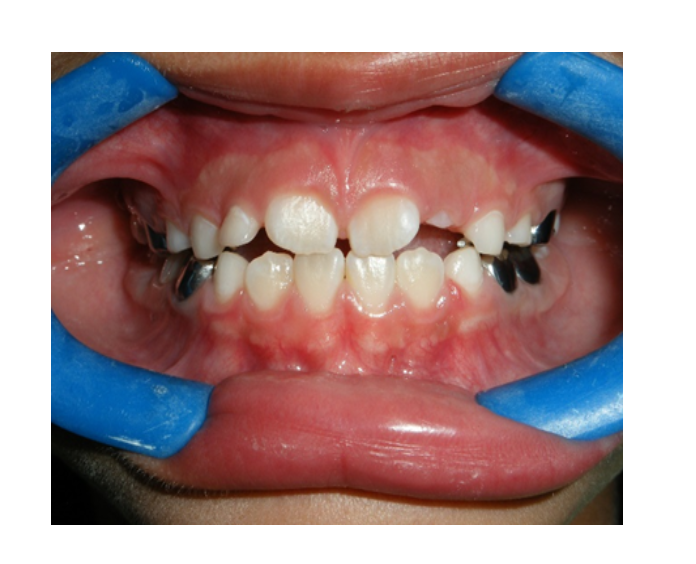

Ortodoncia

temprana